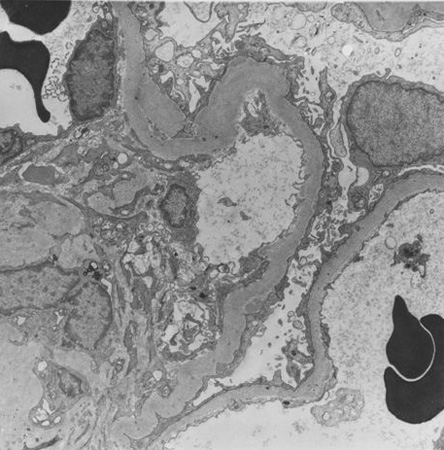

Diabetes mellitus is characterised by high glucose levels and increased glomerular pressure, both of which can cause glomerular mesangium expansion via increased mesangial stretch. Platelet-derived growth factor (PDGF) and transforming growth factor-beta (TGF-beta) mediate mesangial expansion and fibrosis via the stimulation of matrix protein (collagen and fibronectin) synthesis and decreased matrix degradation. Glucose forms advanced glycation end products (AGEs) by binding irreversibly to proteins. Over years, AGEs form crosslinks, stimulate the release of growth factors such as TGF-beta, and cause fibrosis. Angiotensin II (ATII), elevated in DKD, constricts the efferent arteriole in the glomerulus, causing high glomerular capillary pressures, and also stimulates fibrosis and glomerular inflammation. Mesangial expansion is characteristic of early diabetic glomerulosclerosis and is followed by fibrosis in the late stages. Kimmelstiel-Wilson nodules, areas of mesangial expansion on biopsy, are the hallmark of diabetic glomerulosclerosis and are seen in half of the cases of DKD. Increased glomerular basement membrane width, diffuse mesangial sclerosis, hyalinosis, microaneurysm, and hyaline arteriosclerosis are present in addition to tubular and interstitial changes.[17] Hypertension, via mesangial stretch, can aggravate progression of DKD.[Figure caption and citation for the preceding image starts]: Diabetic kidney disease: mesangial expansion due to increased mesangial matrix and decreased degradation of glycosylated collagenFrom the collection of Dr Raoul Fresco; used with permission [Citation ends].

[Figure caption and citation for the preceding image starts]: Diabetic kidney disease: at 12 o'clock - early Kimmelstiel-Wilson nodule, a rounded form of mesangial expansionFrom the collection of Dr Raoul Fresco; used with permission [Citation ends].